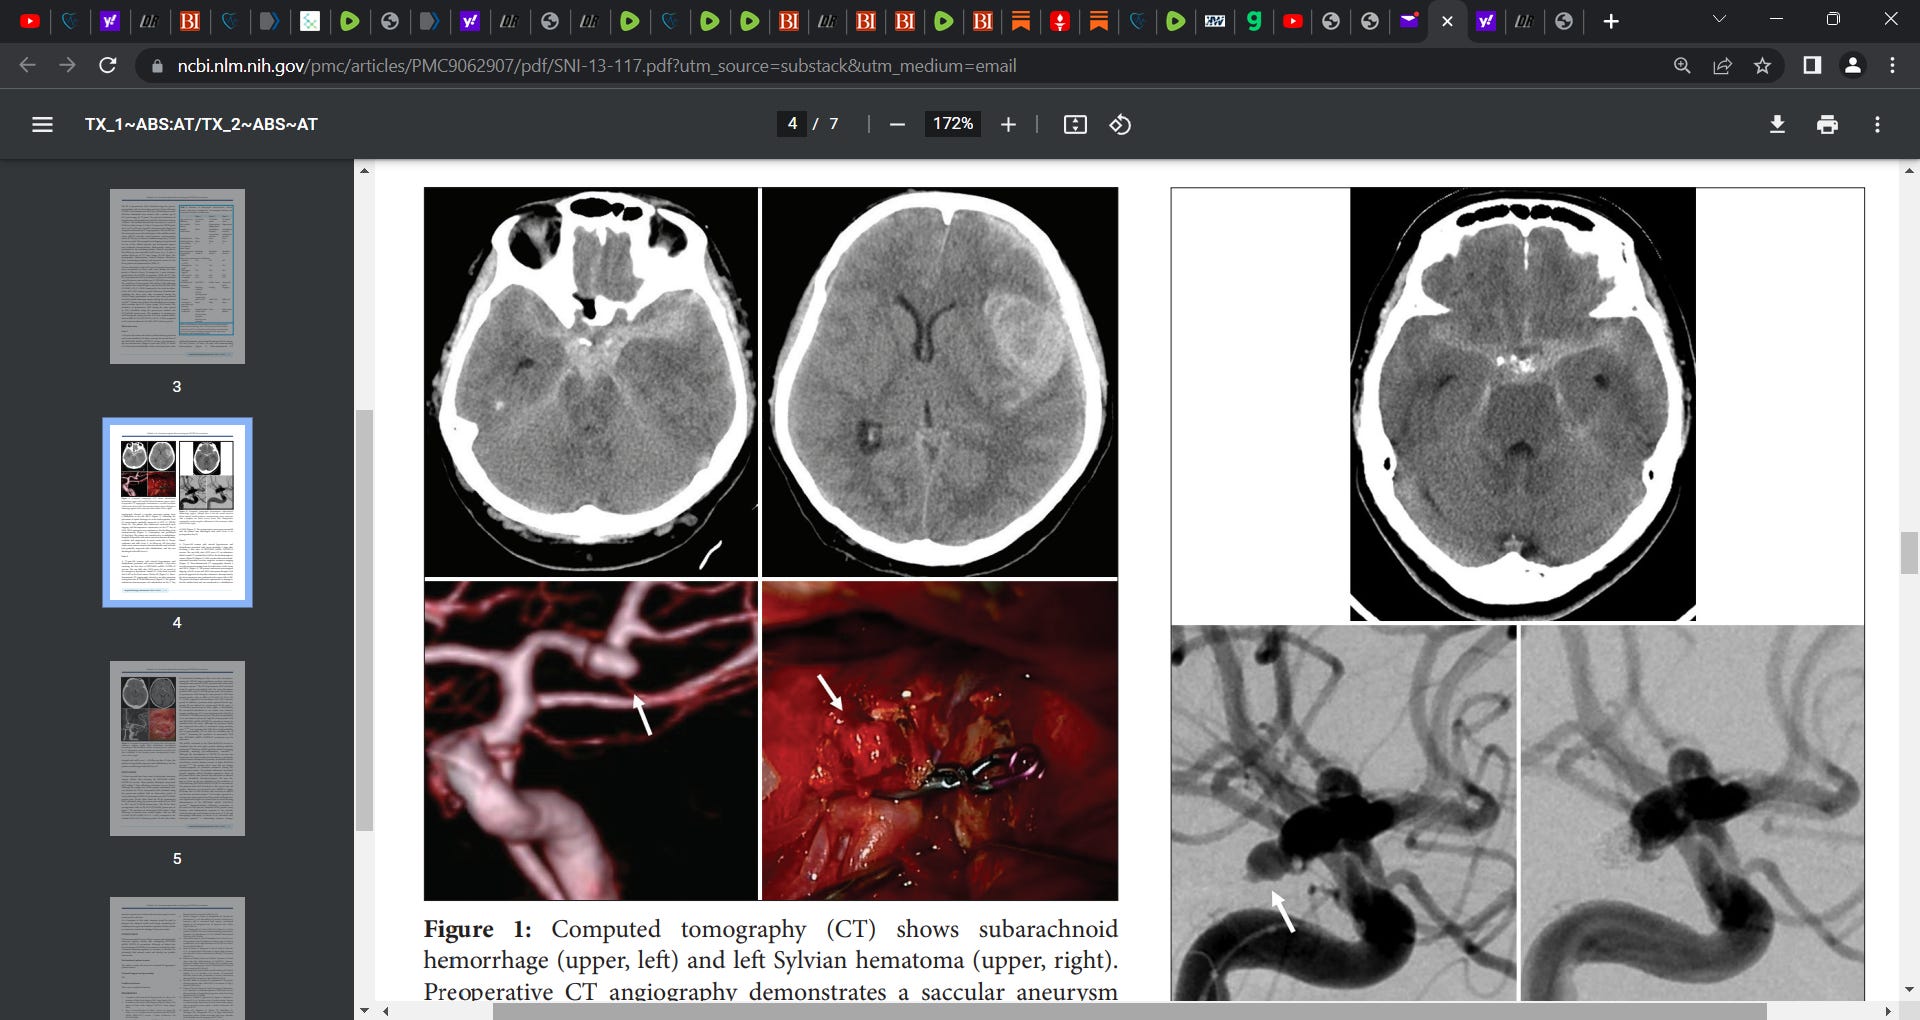

A 44-year-old woman who had no medical history presented with severe headache 4 h after receiving the second dose of the BNT162b2 mRNA COVID-19 vaccine. On admission, she was unconscious (Glasgow coma scale [GCS] 4). Initial CT of the head revealed diffuse SAH in the basal cistern, thin subdural hematoma, intracranial hematoma (blood volume, 34.3 ml; 33 mm × 52 mm × 40 mm), and communicating hydrocephalus [Figure 1]. Three-dimensional CT